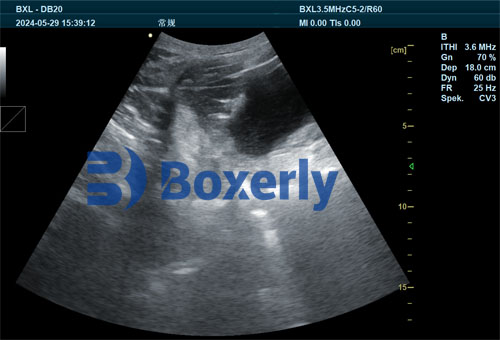

Ultrasound employs high-frequency sound waves to create real-time images of internal tissues. In veterinary practice, ultrasound allows direct visualization of the sow’s reproductive tract without surgery or invasive procedures.

In RP detection, transabdominal or transrectal ultrasound probes are commonly used. The sow is gently restrained, and the probe is applied to the lower abdomen or inserted into the rectum. The ultrasound machine then displays cross-sectional images of the uterus and surrounding structures on a screen.

Healthy postpartum sows show a contracted uterus with no retained membranes visible. In contrast, sows with retained placenta exhibit characteristic ultrasound features such as:

Echogenic (bright) areas inside the uterine lumen indicating placental remnants

Uterine enlargement or fluid accumulation signifying inflammation or infection

Irregular uterine wall texture reflecting tissue damage

By identifying these signs, veterinarians can make an immediate and objective diagnosis of RP, even before clinical symptoms manifest.